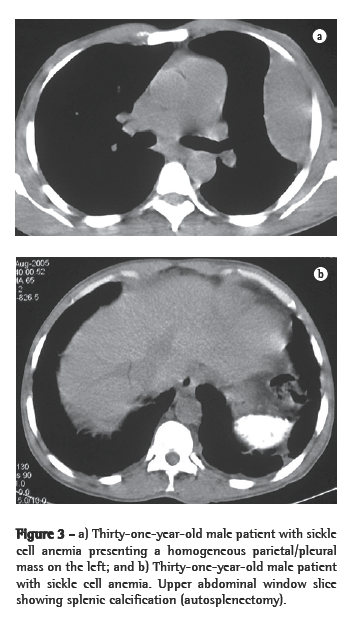

The remaining two patients each presented a parietal pleural mass, both on the left, with no evidence of paravertebral involvement. In one of them, the mass was homogeneous (Figures 3a and 3b), and, in the other, there was associated bone reaction.

As associated findings, two patients presented calcifications in the spleen (Figure 4). Both of them had sickle cell anemia. Two of the six patients had undergone splenectomy, and two presented normal spleen imaging findings. Bone alterations related to the underlying disease were identified in three patients.

On CT scans, masses with dense soft parts, usually homogeneous, with characteristics similar to those described using conventional radiology,(1,2,5,6) and which might or might not be highlighted after administration of contrast material,(4,10) can be seen. This imaging method is important for analyzing the internal structure of the lesions, especially of those that are rich in fat,(5) in order to identify other paracostal masses, and for detecting bone alterations associated with certain hematologic diseases, such as thalassemia and sickle cell anemia.(6) In cases related to thalassemia, sickle cell anemia, or myeloid metaplasia, there can be widening of the medullary cavities of the ribs.(5) All of those aspects were identified in our cases. It is of note that two patients presented calcifications in the spleen, resulting from multiple infarcts, with autosplenectomy. Both of those patients had sickle cell anemia. This finding can also facilitate the differential diagnosis.